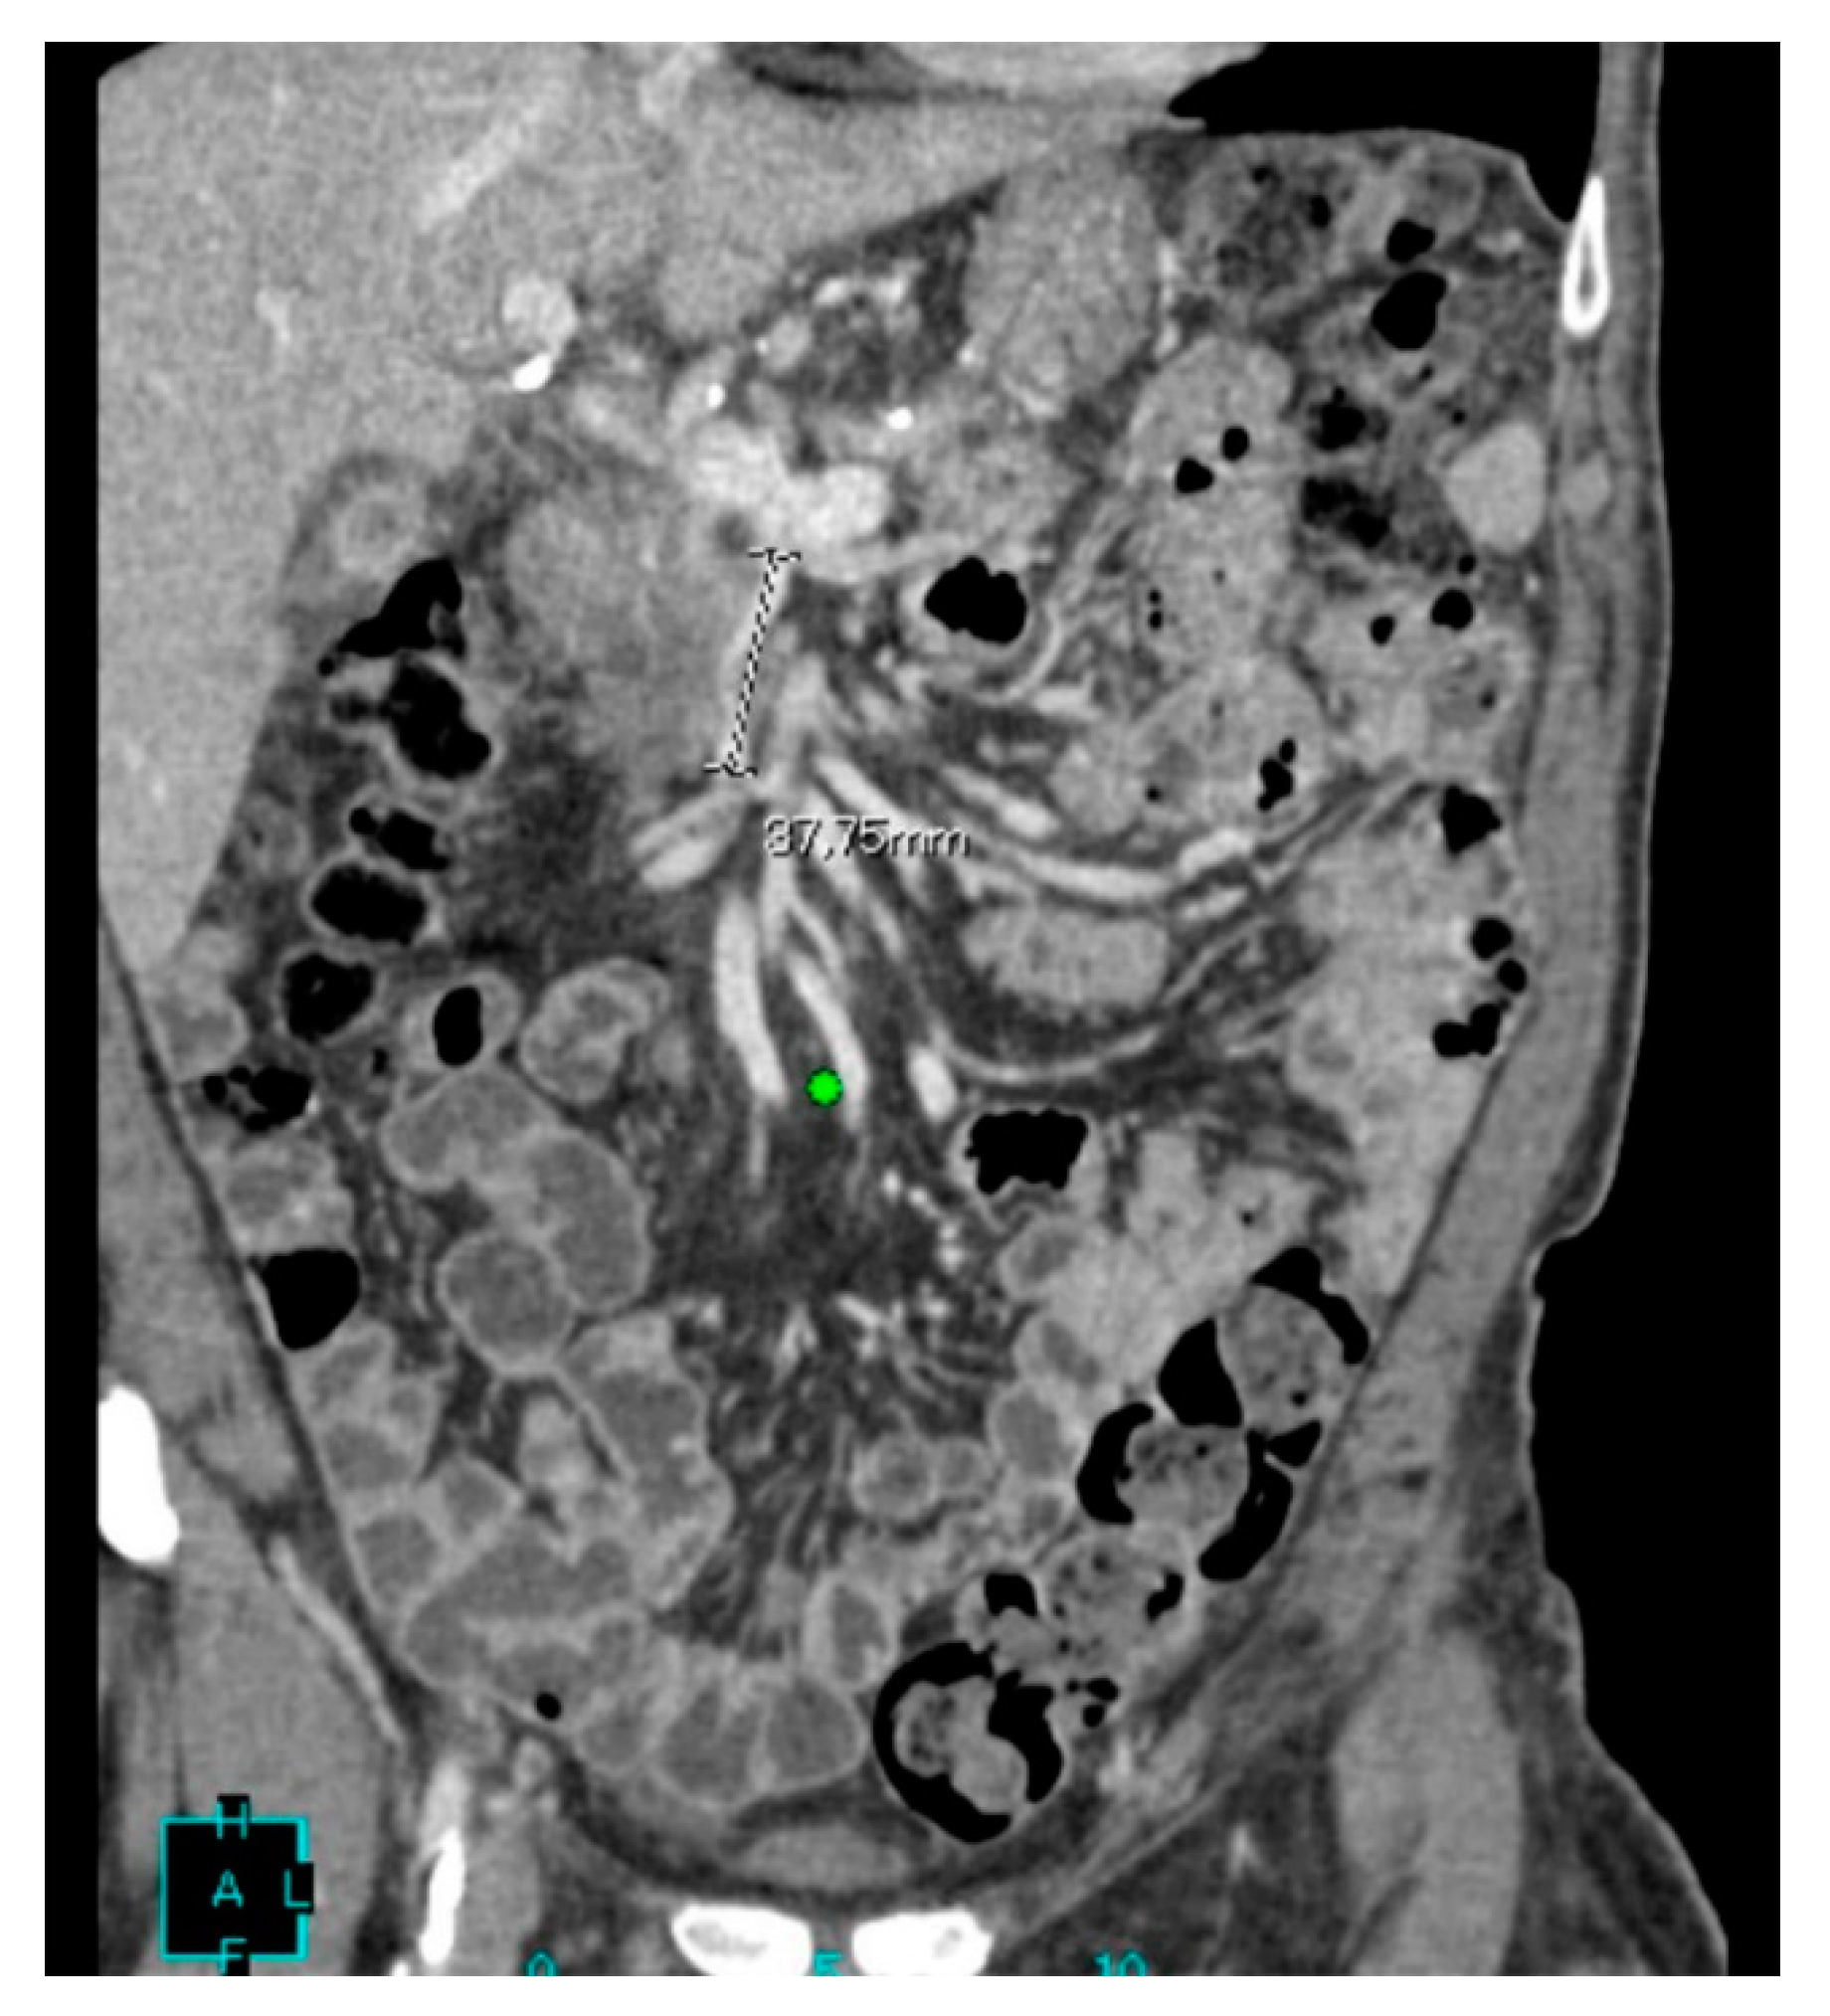

2. Case Presentation